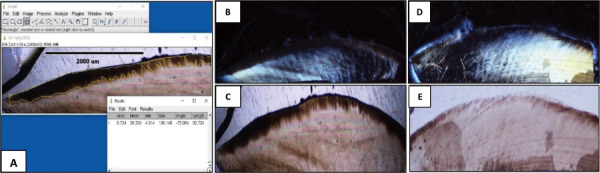

Material and methods: Twenty longitudinal sections of premolars with artificially produced white spot lesions and evaluated with a polarised light microscope. The sample consisted of 20 tooth fragments, which were divided and assigned to two groups: The first group with application of Clinpro TM White Varnish (20 tooth sections) and the second, with MI Varnish TM (20 tooth sections) subjected for 6 days to conditions similar to the oral cavity. The sections were then re-evaluated by calculating the lesion depth and remineralization area (Image J software). Student' s t-test was used to analyse the data.

Results: MI Varnish TM fluoride varnish achieved a greater remineralization area than Clinpro TM White Varnish (838042.6±140359.3 μm2 and 678313.8±137265.7μm2, respectively), with a statistically significant difference (p<0.05).

Conclusions: MI Varnish TM had a better effect than Clinpro TM White Varnish in remineralizing lesions, in vitro, in the enamel of young permanent teeth with caries in the white-stained phase. Key words:Fluorides varnishes, histological effect, dental remineralization, polarised light microscope.